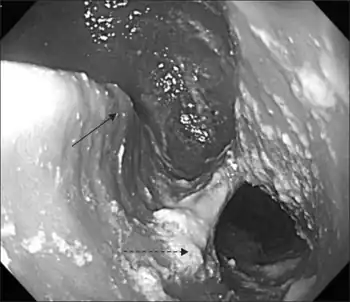

A Killian–Jamieson diverticulum is an outpouching of the esophagus just below the upper esophageal sphincter.[1]

The physicians that first discovered the diverticulum were Gustav Killian and James Jamieson. Diverticula are seldom larger than 1.5 cm, and are less frequent than the similar Zenker's diverticula. As opposed to a Zenker's, which is typically a posterior and inferior outpouching from the esophagus, a Killian–Jamieson diverticulum is typically an anterolateral outpouching at the level of the C5-C6 vertebral bodies, due to a congenital weakness in the cervical esophagus just below the cricopharyngeal muscle. It is usually smaller in size than a Zenker's diverticulum, and typically asymptomatic.[2] Although congenital, it is more commonly seen in elderly patients.[3]